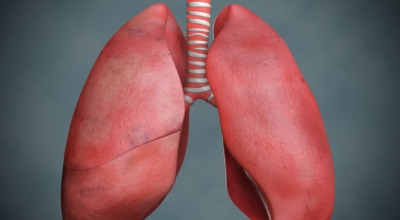

폐란?

척추동물 중 공기호흡을 하는 동물의 호흡기관으로, 허파 또는 폐장이라고도 하며, 구조적으로 기관지와 혈관이 모여 이루어져 있습니다. 폐는 산소와 이산화탄소(탄산가스)를 교환하는 가장 중요한 기관입니다. 사람에게는 좌우 한 쌍이 있으며, 전체적으로 반원뿔 모양을 하고 있습니다. 흉강 중앙에 있는 종격을 사이에 두고 가슴의 좌우에 자리 잡고 있는데, 좌측에 심장이 있어 오른쪽 폐가 조금 더 큽니다.